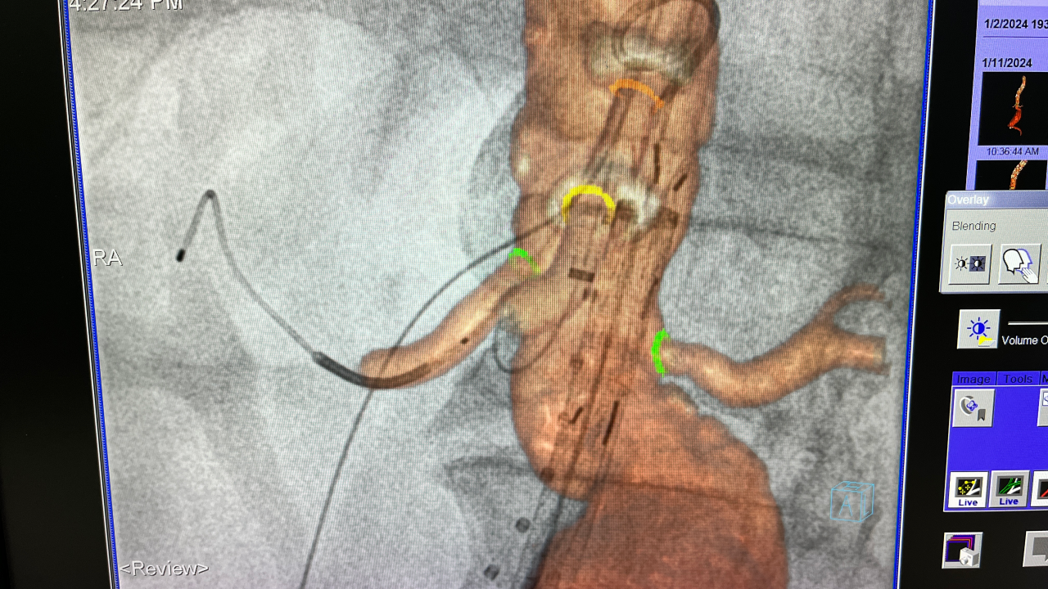

以不同颜色的醒目圆圈标记双肾动脉、肠系膜上动脉、腹腔干开口

3D影像融合技术的关键步骤

影像配准:根据术中实时影像对3D影像进行必要的微调校正。

3D影像引导下完成窗口超选、置管及确认

3D影像融合

3D影像引导下,

主体支架窗口与弓上三分支开口对位

依次超选无名、左颈总及左锁骨下动脉